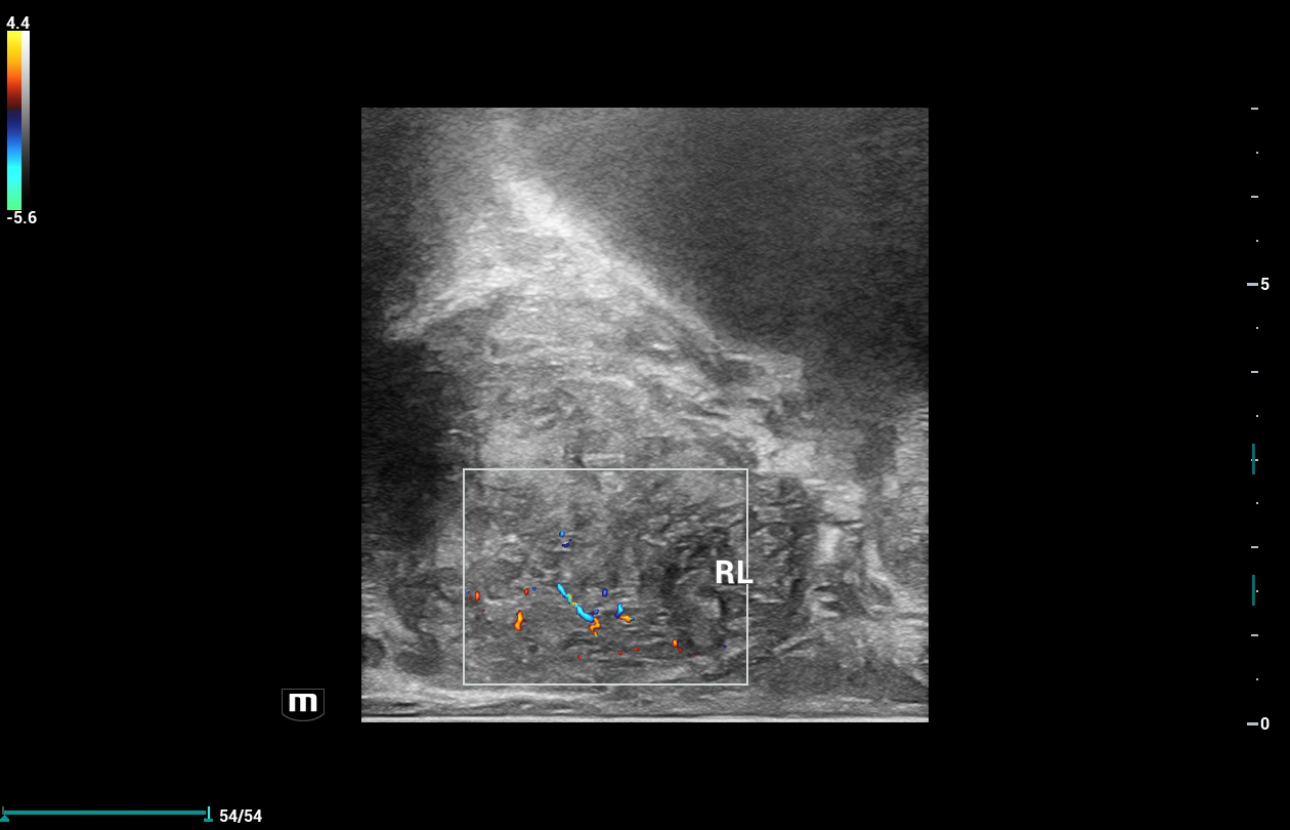

초음파

2D color 초음파는 RL에서 고혈관계 및 캡슐 불규칙성이 의심되는 저에코 영역을 보여 주었지만, 좌엽 소견에서는 정상적이었으나 약간 고르지 않은 캡슐도 발견되어 우엽과 좌엽 양쪽 전립선 전체에 전립선암이 발생했는지, 우엽에만 발생했는지 정확하게 진단하기 어려웠습니다.